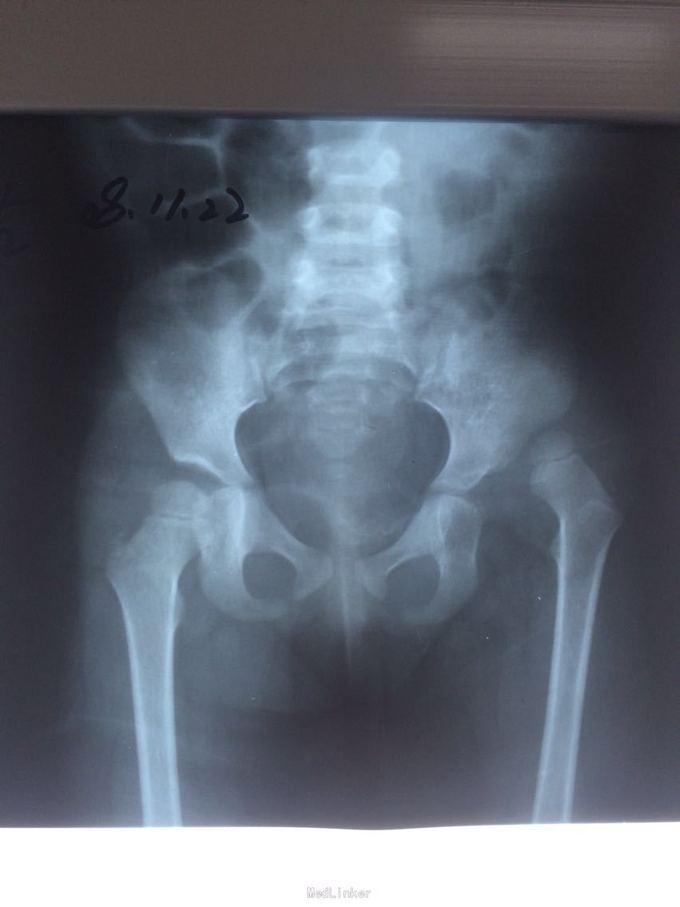

患者11岁,手术治疗效果怎么样

自幼左髋关节脱位